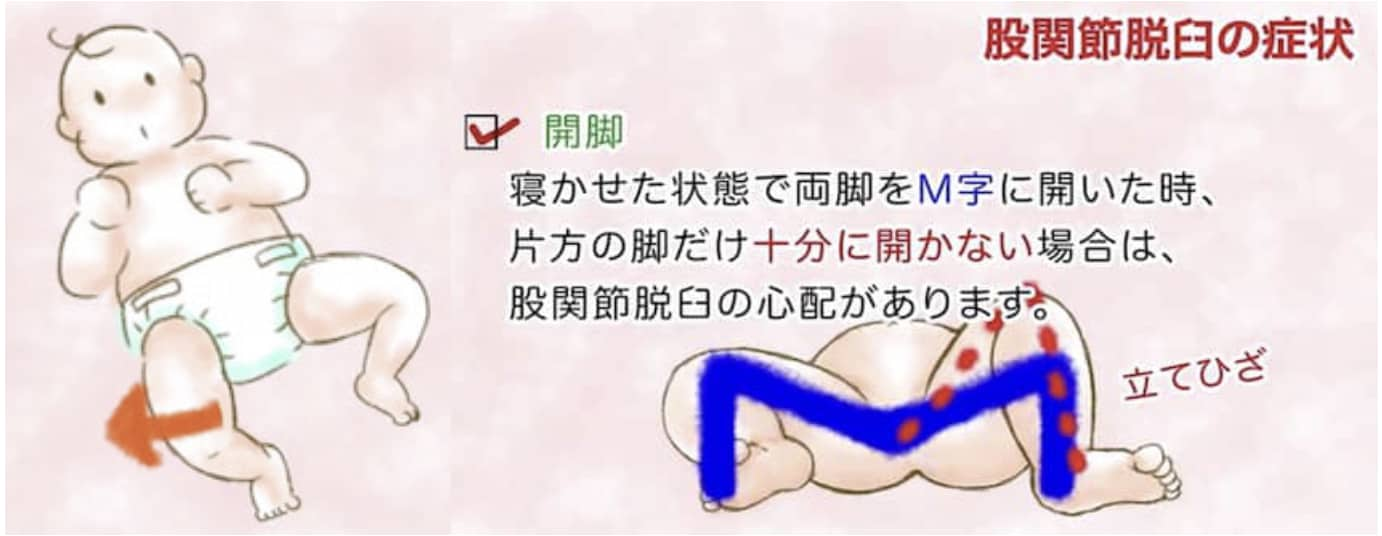

外傷による脱臼と違って、脚の痛みや動かしにくさを訴えることはありません。歩き始める時期が遅れることも稀なので、脱臼していても気付かれないことがあります。赤ちゃんの頃に脱臼を疑う症状としては、立て膝(特に向き癖の反対側)、股関節が開きにくい、しわの左右差などがあります。歩き始めてからは姿勢や歩き方の異常で発見されます。詳しくは「自宅でできる股関節チェック」をご参照下さい。

② 脚の開き(開排制限)

股関節の開きにくさ(開排制限)を調べます。両膝を合わせた状態からゆっくり開いていきます。女児 80度、男児 70度以上開くのが正常です。開きが悪いときには脱臼の可能性があります。女児は関節が柔らかいので脱臼があっても開排制限がないこともあります。

股関節の開きにくさ(開排制限)を調べます。両膝を合わせた状態からゆっくり開いていきます。女児 80度、男児 70度以上開くのが正常です。開きが悪いときには脱臼の可能性があります。女児は関節が柔らかいので脱臼があっても開排制限がないこともあります。

いつも顔が同じ方ばかり向いて寝る「向き癖」と脱臼には関連があります。向き癖があると、反対側の脚が立て膝になるので、股関節の動きが制限されるため脱臼しやすくなるります。脱臼は左側に多いのですが、それは右の向き癖が多いからといわれるほど、強く関連しているので、向き癖は治しておきましょう。

いつも顔が同じ方ばかり向いて寝る「向き癖」と脱臼には関連があります。向き癖があると、反対側の脚が立て膝になるので、股関節の動きが制限されるため脱臼しやすくなるります。脱臼は左側に多いのですが、それは右の向き癖が多いからといわれるほど、強く関連しているので、向き癖は治しておきましょう。